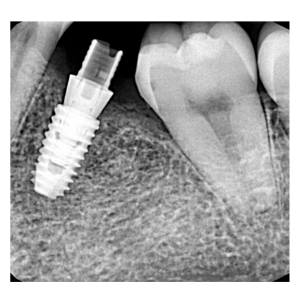

治療途中のインプラント症例

治療途中のインプラント症例です。

抜歯した部分を噛める様にしたい |

46歳 男性 |

1時間 |

¥350,000(税別) |

腫れ・痛み・神経損傷・インプラント周囲炎・骨吸収 など |